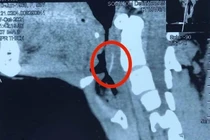

Hóc xương hay hóc dị vật không phải là một bệnh lý, tuy nhiên nếu không được phát hiện và xử trí kịp thời sẽ rất nguy hiểm, có thể gây áp xe cổ, áp xe cổ lan trung thất… gây ảnh hưởng nghiêm trọng đến sức khỏe người bệnh.

BVĐK Xuyên Á vừa cấp cứu một cụ ông 73 tuổi, bị hóc xương cá nhưng không biết, chiếc xương trôi xuống ruột non, đâm thủng thành ruột gây nhiễm trùng máu, viêm phúc mạc nặng.

Bệnh viện Tai Mũi họng T.Ư đã phẫu thuật ca hóc xương cá hiếm gặp sau 20 ngày xương cá nằm trong bó mạch cảnh. Các bác sĩ đã phải rất khó khăn tìm và lấy thành công chiếc xương dài 3cm này.